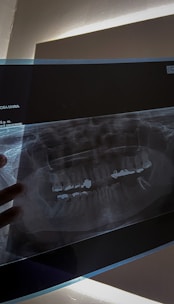

Dental clinics in Punawale use modern technology and techniques to perform root canal procedures. They use digital X-rays to diagnose and plan the procedure, and special tools to clean and shape the root canals. This helps to improve the success rate of the procedure and minimize the risk of complications.